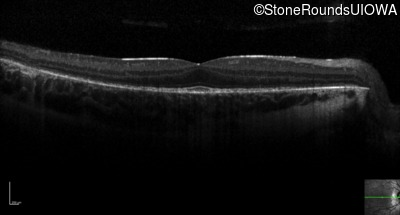

Optical Coherence Tomography - Right - 20/20 -3

Exemplar / OCT Stack

OCT Stack